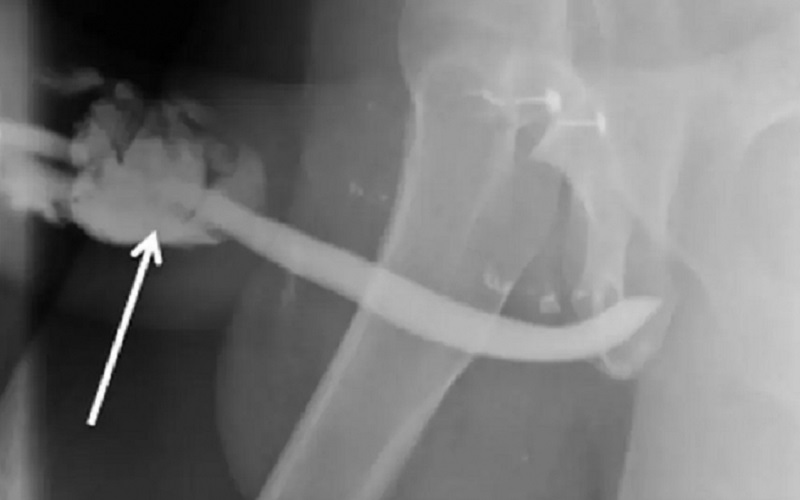

(Foto:Reprodução / International Journal of Surgery Case Report ) – Caso foi registrado na Tanzânia e o paciente, que não foi identificado, precisou passar por uma cirurgia de emergência

Aos médicos, o paciente revelou que a companheira estava por cima dele no momento em que ouviu um “estalo”. O pênis escorregou e atingiu a área perineal da mulher enquanto ela tentava recolocá-lo. O homem sofreu três fraturas e, segundo ele, no mesmo instante perdeu a ereção, sentiu dor, saiu sangue pela uretra e o pênis inchou.

O paciente passou por uma cirurgia de emergência em um hospital de Kilimanjaro. Nos relatos dos médicos, a fratura teria deixado o pênis semelhante a um balão. No entanto, a recuperação foi rápida. Após três dias no hospital, o homem teve alta. Em casa, ele precisou usar um cateter por quase três semanas. Depois de seis meses o homem foi a uma consulta médica e disse que já havia retomado a vida sexual sem dificuldades. Apesar do pênis não ter ossos, os médicos usaram o termo “fratura” para definir a chamada ruptura da túnica albugínea, que é o tecido fibroso que mantém o sangue em circulação durante o momento de ereção. Para os médicos, a fratura também pode acontecer durante uma ereção noturna ou em uma masturbação.